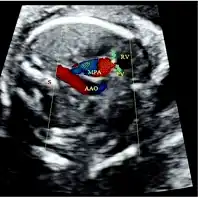

Doppler resolved this problem by visualizing the retrograde flow in the MPA , indicating pulmonary valve atresia

Ventricular septal defect via echocardiogram